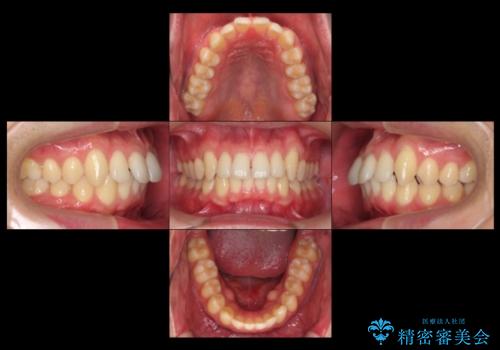

- 前歯のすき間を気にして来院。

矯正治療か、セラミックで最短で治すかの選択肢を提示し、セラミックで治すことにしました。

利点は、早く終わる上に、保定の必要がないため負担が少ないことが挙げられます。

ただし、セラミックは欠ける特性があるため、夜はナイトガードを使用していただくことにしました。

全て神経は取らずに、削りました。

長年コンプレックスだったすき間が閉じたとのことで、喜んでいただきました。